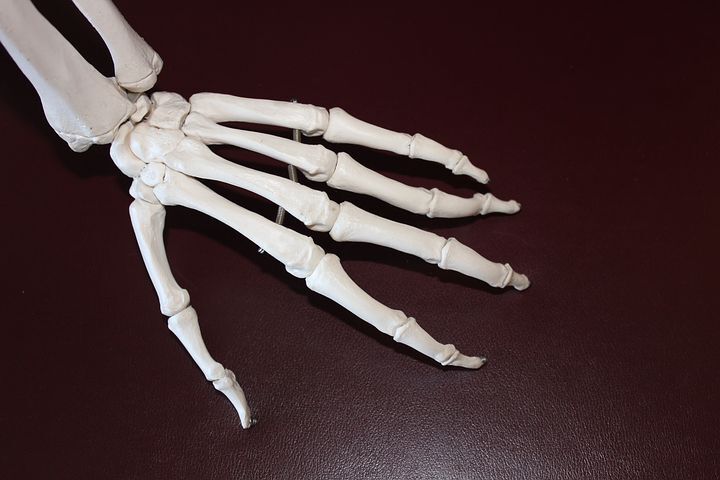

류마티스 관절염은 면역체계에 이상이 생겨 관절에 염증이나 부종등 심한 통증을 수반하게 되는데요. 연골과 뼈가 손상을입어 관절이 변형되고 관절의 기능이 저하되는 질환이라 할수 있습니다.

초기증상으로 손이나 발가락의 관절이 대칭으로 부어올라 아침에 굳어지는 경향을보입니다. 발열과 나른함, 식욕 저하 등 전신 증상으로 나타나기도 하는데요.

손이나 발가락 같은 작은 관절에 발병하는 경우가 많다고 볼수 있지만, 기간이 길어지면서 무릎이나 어깨ㆍ허리 등의 큰 관절에 염증이 전이되는 경우가 대부분입니다. 아직까지 왜 이런 증상들이 일어나는지 완벽하게 밝혀지지는 않았지만, 유전 적 요인과 흡연 습관, 잇몸 질환과 관련이 있다고 보고되고 있습니다.

류마티스 관절염 증상 초기에는 좌우 대칭으로 손가락과 발가락의 관절이 붓고, 아침에 경직을 느끼게 일반적이라 할수 있습니다. 시간이 흐름에따라 관절이 파괴되면, 작은 관절도 생활에 큰 불편함을 초래하게 되는 것입니다.